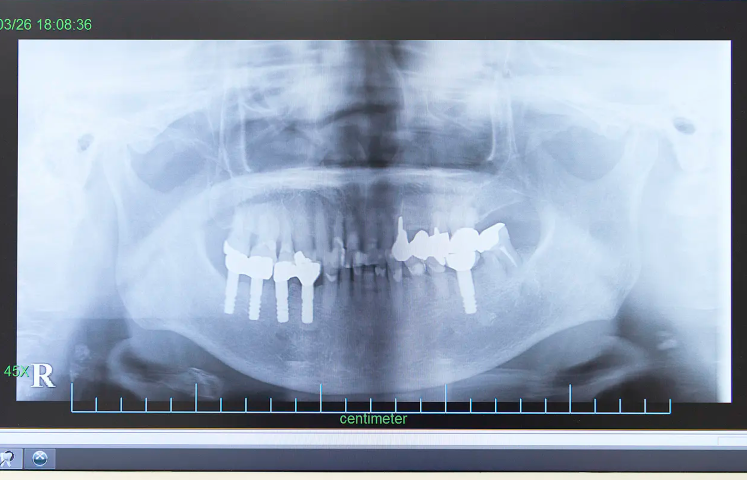

安心・安全を第一に、大学病院の経験を活かしたインプラント治療

CTと20年の技術が支える、確かなインプラント治療

CTと20年の技術が支える、確かなインプラント治療

中川歯科医院では、神戸大学附属病院で口腔外科の経験を積み、インプラント治療に20年以上携わってきた院長が、すべての症例を担当しています。外科手術を伴うインプラント治療は高度な技術と正確な診断が求められる分野であり、実績豊富な歯科医師による対応が安心感に直結します。

治療前には歯科用CTを用いて、あごの骨や神経、血管の位置を3次元で立体的に把握。患者様のお口の状態を正確に診断し、リスクを最小限に抑えた治療計画を立案します。また、治療後もインプラントのメインテナンスを丁寧に行い、長期的にトラブルのない使用を目指します。

中川歯科医院では5年間の保証制度も設けており、治療後の被せ物に不具合が生じた場合でも安心です。これは長年の治療実績に裏打ちされた、技術と品質への自信の証です。

「入れ歯では噛みにくい」「見た目を自然にしたい」といったお悩みに、外科的技術と丁寧な診断でお応えする中川歯科医院のインプラント治療は、幅広い世代の患者様にご支持いただいています。

治療前には歯科用CTを用いて、あごの骨や神経、血管の位置を3次元で立体的に把握。患者様のお口の状態を正確に診断し、リスクを最小限に抑えた治療計画を立案します。また、治療後もインプラントのメインテナンスを丁寧に行い、長期的にトラブルのない使用を目指します。

中川歯科医院では5年間の保証制度も設けており、治療後の被せ物に不具合が生じた場合でも安心です。これは長年の治療実績に裏打ちされた、技術と品質への自信の証です。

「入れ歯では噛みにくい」「見た目を自然にしたい」といったお悩みに、外科的技術と丁寧な診断でお応えする中川歯科医院のインプラント治療は、幅広い世代の患者様にご支持いただいています。